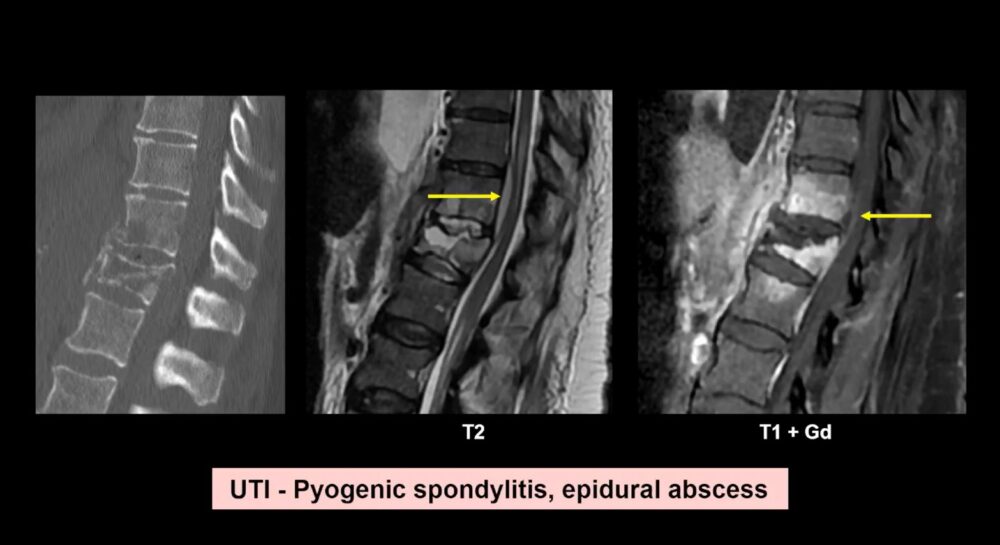

Moreover, falls in the elderly are often complicated by underlying medical conditions, such as strokes or infections, which may have caused the fall in the first place. In some cases, pneumonia or other respiratory conditions resulting from prolonged lying on cold floors can be identified through imaging. Dr. Blanco Barrio shared cases of aspiration pneumonia that were detected through CT scans, emphasizing how important it is to investigate these possibilities during imaging.